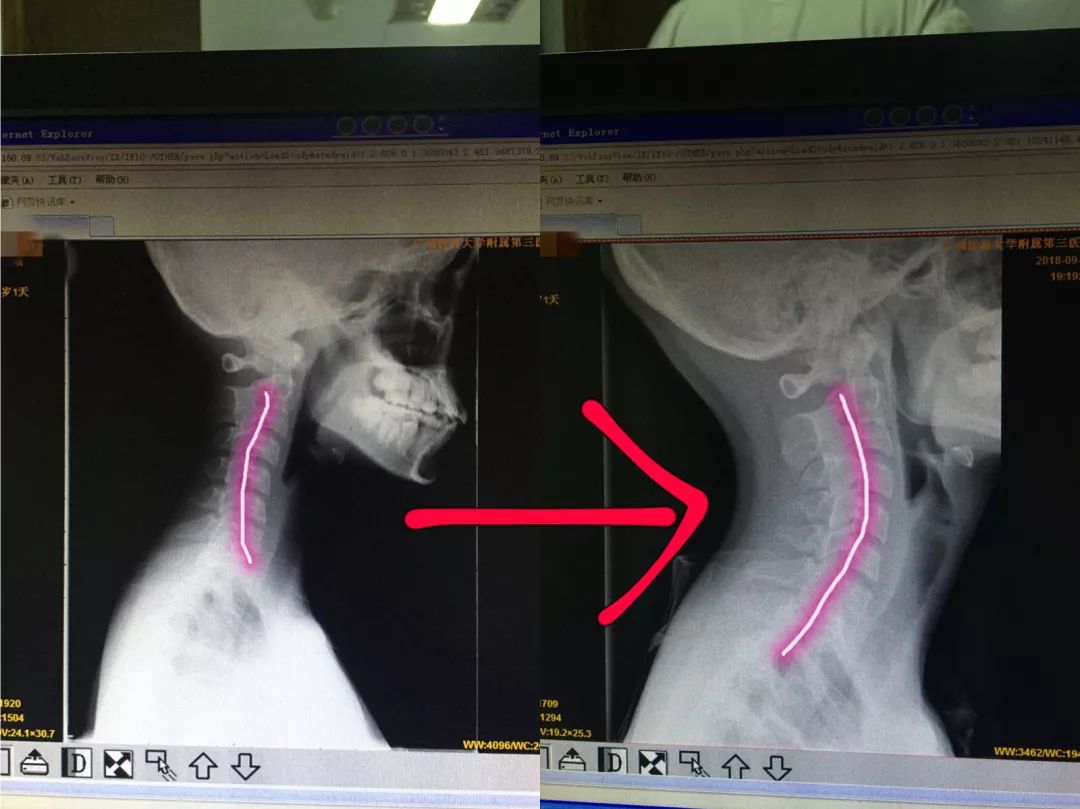

Mar 23, 14 · 反弓的人很多,但有症状的人并不多。也就是说,你的颈椎也许早就反弓了,只是最近才出现了症状。经过正确的治疗,症状应该会很快消失的,但反弓不会很快纠正,不过这也没什么大不了的,今后只要注意消除引起反弓的原因(长期低头或枕头高)就行了。治疗方案: 1龙氏"平头摇正法"整复颈椎关节错位。 2龙氏"仰卧推正法"调整颈轴反弓状态,逐步恢复颈椎自然生理曲度。 3嘱日常工作避免长时间低头工作,每半个小时活动颈肩肌肉。 4嘱游蛙泳,多锻炼颈后部肌肉,调整反弓的颈椎。Dec 06, · 加强颈椎抗阻力前曲后伸功能锻炼,适当牵引治疗。

Aug 29, 16 · 康复保守治疗。 产生颈椎反弓的朋友不必过于慌张,90%颈椎反弓的患者可以通过康复治疗减轻甚至消除不良症状,改善颈椎曲度。 1、理疗 :传统的颈椎牵引、超短波、干扰电等理疗方式于炎症的消除、疼痛的控制有一定作用。Oct 11, 18 · 颈椎反弓目前非常常见,尤其见于初高中生。 以前颈椎反弓常见于6070岁的高龄的老年人,现在随着课业加重,很多学生也都出现颈椎反弓。 颈椎反弓不是完全无法治疗,治疗方法如下:1、Sep 12, 15 · 颈椎反弓怎么办?这是怎么引起的?4611阅读;